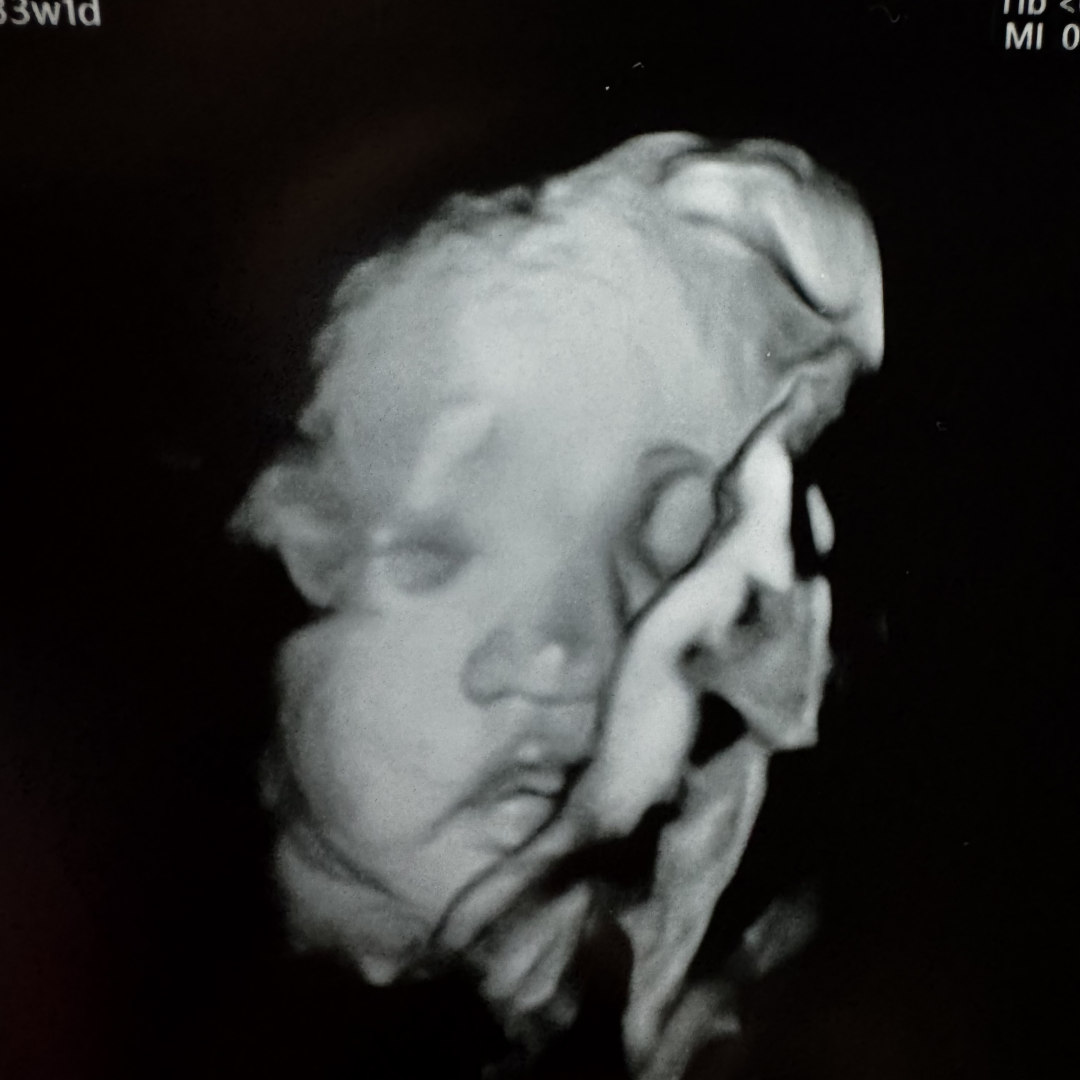

Gwendolyn Mae